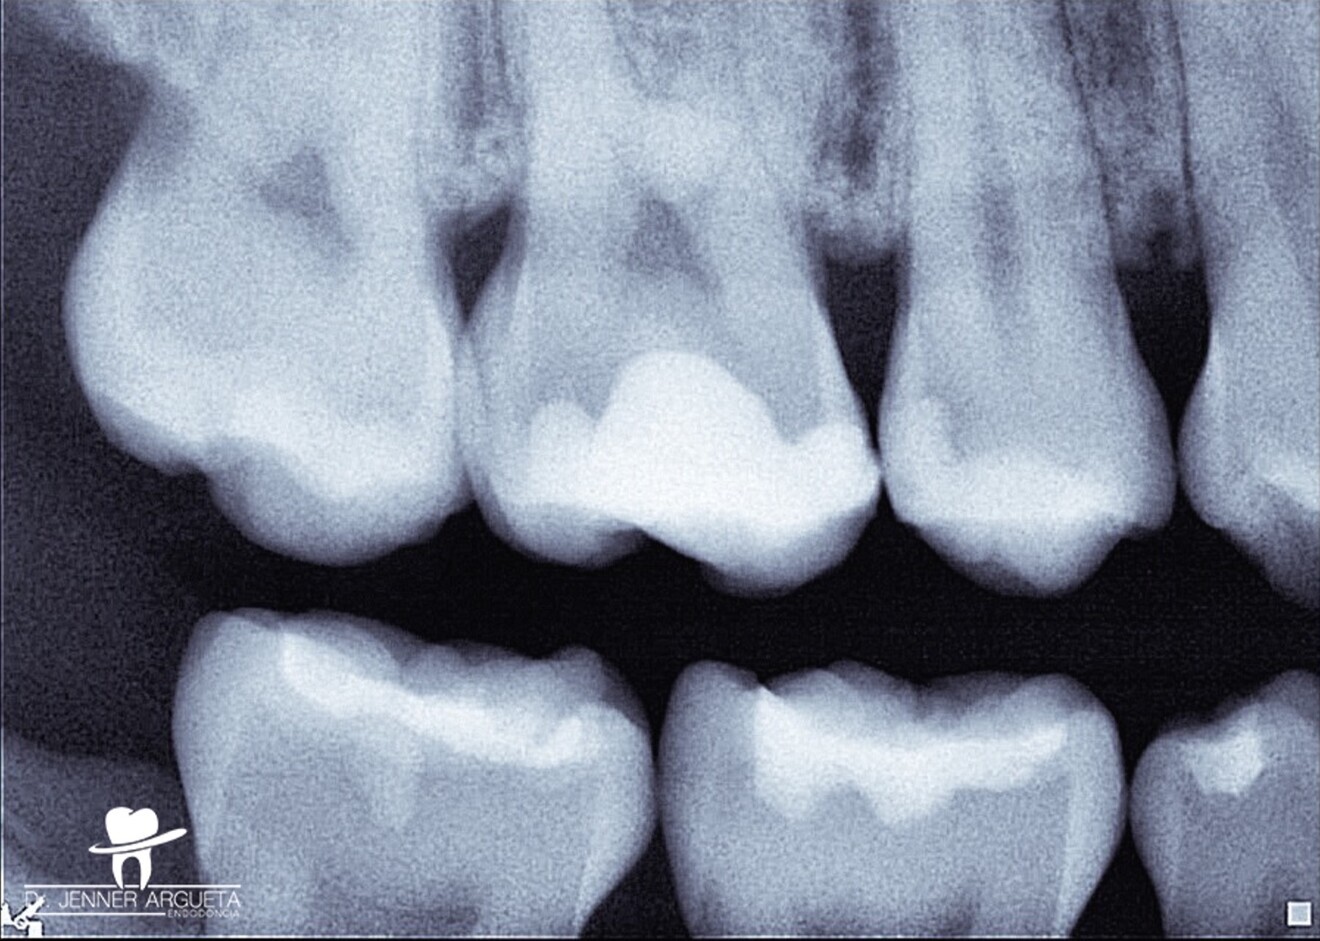

Fig. 2: Bitewing radiograph showing evidence of a deep restoration in tooth #16 at mesial level. Under-mineralised tissue was found close to the mesial pulp horn.

The patient attended reporting short-term pain in tooth #16 (Fig. 1). Through radiography, clinical assessment and an analysis of the patient’s clinical history, reversible pulpitis was diagnosed, and a deep Class II temporary restoration was found (Fig. 2).